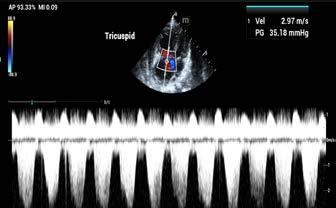

Post-mortem thoracic radiographs were performed. They showed an elliptical radiolucent focus measuring approximately 7cm in height and 3.5cm in length superimposed over the region of the right ventricle in lateral views (Figures 2 and 3).

The clinical presentation and thoracic radiographs support a diagnosis of venous air embolism.

In this unfortunate case, the iatrogenic rent in the axillary vein allowed air to enter the central venous system down a gravitational gradient to the right side of the heart. This resulted in outflow obstruction to the right ventricle, hypocapnia, hypoxaemia, hypotension, reduced cardiac output and ultimately cardiac arrest.

Figure 2. Lateral thoracic radiograph showing air in right ventricleThere are no minimally invasive aids with high sensitivity and specificity for diagnosing VAE. Transoesophageal echocardiography is the most sensitive technique for detecting VAE, being able to detect 0.02mL/kg of air. Precordial doppler ultrasound is another sensitive technique for detecting VAE, whereby the anaesthetist listens for a characteristic ‘drum-like’ or ‘mill-wheel’ murmur associated with VAE.